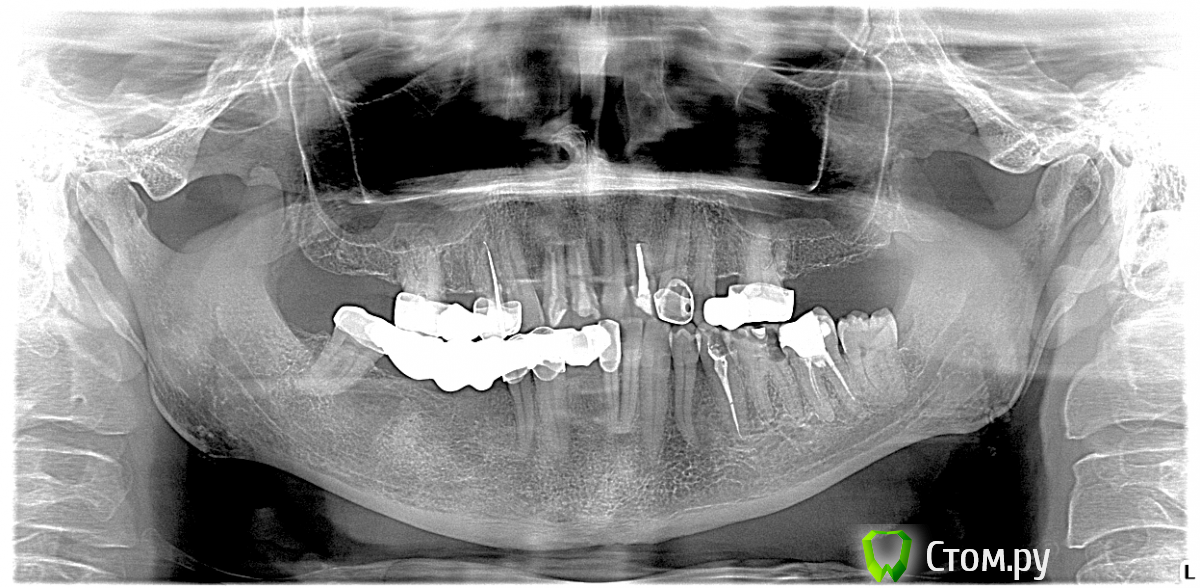

urseva19.05.10 Опубликовано 2 сентября, 2014 Поделиться Опубликовано 2 сентября, 2014 Обратился ко мне родственник для проведения профилактического осмотра. Я направил на панорамный снимок и ...Имплантаты ставили 12 лет назад и металлокерамические коронки соответственно тоже.Нас учили:1) Пластинчатые имплантаты мягко скажем г...но2) Протяженные мосты на имплантаты не устанавливать, да и вообще раньше говорили один имплантат одна коронка.3) Коронки на имплантатах не в коем случае несвязывать с интактными или лечеными зубами.Мосты стоят не шолохнутся, даже микро подвижности нет.Хотелось бы услышать ваше мнение, как такое могло получиться. И с чем бы вы это связали. Спасибо!Импланты.bmp Ссылка на комментарий

TIGER Опубликовано 2 сентября, 2014 Поделиться Опубликовано 2 сентября, 2014 Я не вижу на этом снимке ничего хорошего.....всё чему учили потверждается в вашем случае на снимке Ссылка на комментарий

Bier Опубликовано 2 сентября, 2014 Поделиться Опубликовано 2 сентября, 2014 У пластин вероятность интеграции 30% и куча заморочек с протезированием, а так безусловно прекрасные имплантаты )) 4 Ссылка на комментарий

urseva19.05.10 Опубликовано 2 сентября, 2014 Автор Поделиться Опубликовано 2 сентября, 2014 Я не вижу на этом снимке ничего хорошего.....всё чему учили потверждается в вашем случае на снимкеУ вас есть отдаленные результаты имплантации и протезирования до 10-12 лет? Разве не хорошо что человек затратив на тот момент не очень то и много денег пользуется не съемными конструкциями столько лет, да еще и попользуется судя по ситуации во рту? 1 Ссылка на комментарий

urseva19.05.10 Опубликовано 2 сентября, 2014 Автор Поделиться Опубликовано 2 сентября, 2014 Неужели даже в первом сегменте все так замечательно клинически?У меня был пациент с мостом 17-пластиночный имплант-12. Тоже стоял много лет, момт неподвижный. Как мост распилил, имплант с коронками сам выпал из десны практически. Зубы (резорциненные похоже) по-прежнему неподвижны, а имплант давно несостоятелен и дефект костный громадный.Другой случай был: имплант такой интегрировался, но сломался. После выпиливания пьезо с тонкой насадкой тоже получился очень приличный дефект который потребовалось восстанавливать блоком.Вобщем впечатления от пластинок не очень, хотя сам не ставил.В любом случае если имплантат не состоятелен должна быть хоть какая то подвижность. А здесь все крепко стоит. Я не в коем случае не защищаю пластинчатые имплантаты или соединение со своими зубами, просто хочу сказать что при должной сноровке, соблюдении протокола и использовании всего того что нас учили в хирургии и ортопедии современные имплантаты должны стоять всю оставшуюся жизнь. Ссылка на комментарий